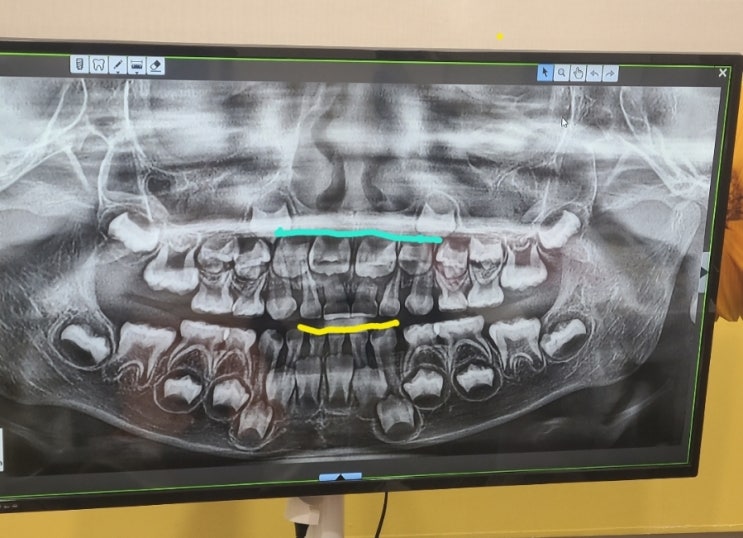

가철식 악궁확장장치

친구의 아들이 지난 3월부터 악궁확장장치를 하고있는데, 나도 소개해달라고 부탁하여 치과에 가보게 되었...